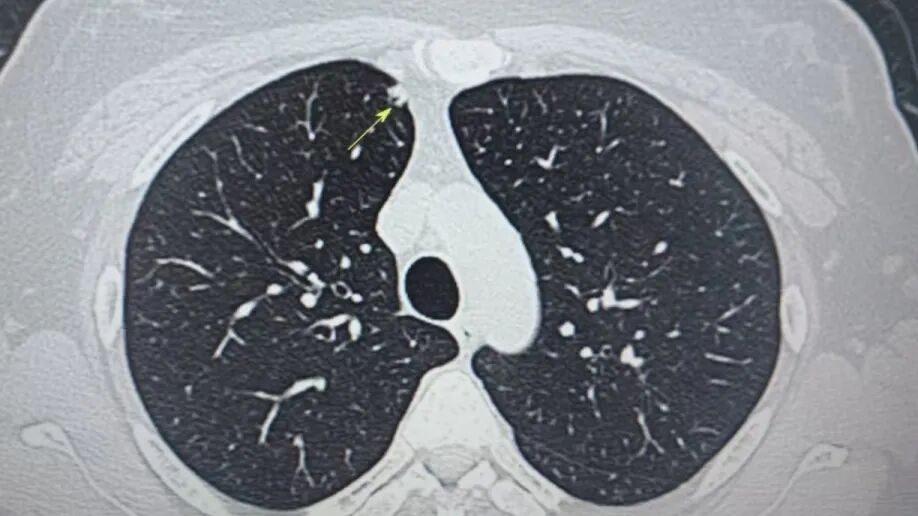

内容提要 近年来,肺结节检出率持续攀升,其发病群体正呈现明显年轻化趋势,更令人警醒的是,有些结节虽小,却暗藏致命风险。葫芦岛市第二人民医院肺结节诊治中心近期接诊的35岁刘女士(化名)便是典型一例:她体内两颗直径仅4mm和6mm的“迷你”结节,竟被病理证实为恶性肿瘤!这一案例再次颠覆了公众对“结节小=安全”的固有认知。 专业研判 为生命赢得转机 微创精准切除 四级手术显实力 小结节≠低风险 认知误区亟需破除 人民医院 人民名医